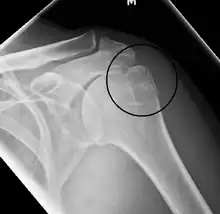

A fracture of the greater tuberosity as seen on AP X ray

A fracture of the greater tuberosity of the humerus